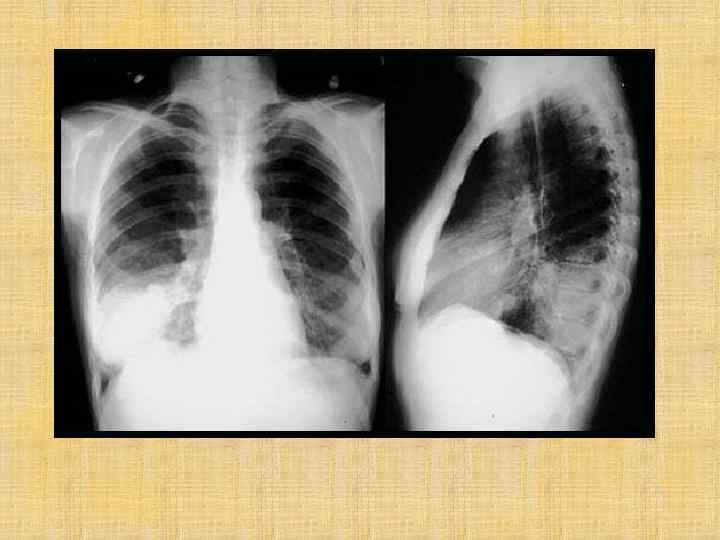

Рентгенография грудной клетки Эксудативный плеврит левосторонний Пневмония, осложненная внутрилегочной деструкцией Буллезная форма деструктивной пневмонии Очаговая пневмония